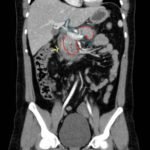

Computed tomography of the abdomen and pelvis with contrast show edema of the pancreas (red outline) and duodenum (yellow arrow) with peripancreatic inflammation, fluid and fat stranding (blue highlight). The distal pancreatic tail was noted to appear normal (green arrow). There was no organized drainable fluid collection, and no parenchymal hypo-enhancement. These findings are consistent with moderate severity acute interstitial pancreatitis.